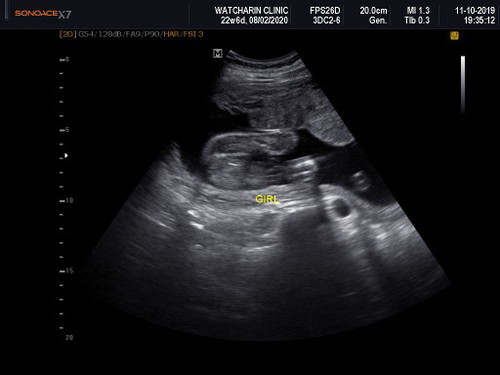

ซาวด์เพศลูก

เดือนที่แล้วหมอบอกได้ลูกสาว เดือนนี้หมอบอกได้ลูกชาย ??สรุปคือ เราควรจะเชื่อหมอ หรือรอตอนคลอดทีเดียวเลยคะ

รอดูอายุครรภ์เรื่อยๆค้ะ ถึงเห้นชัดเจน อัลตร้าซาวด์ก้อชัวแล้วค้ะ อยู่ที่ว่าจะชัดรึป้าว.

คือน้องยังเลกเลยดูไม่ชัดค่ะ